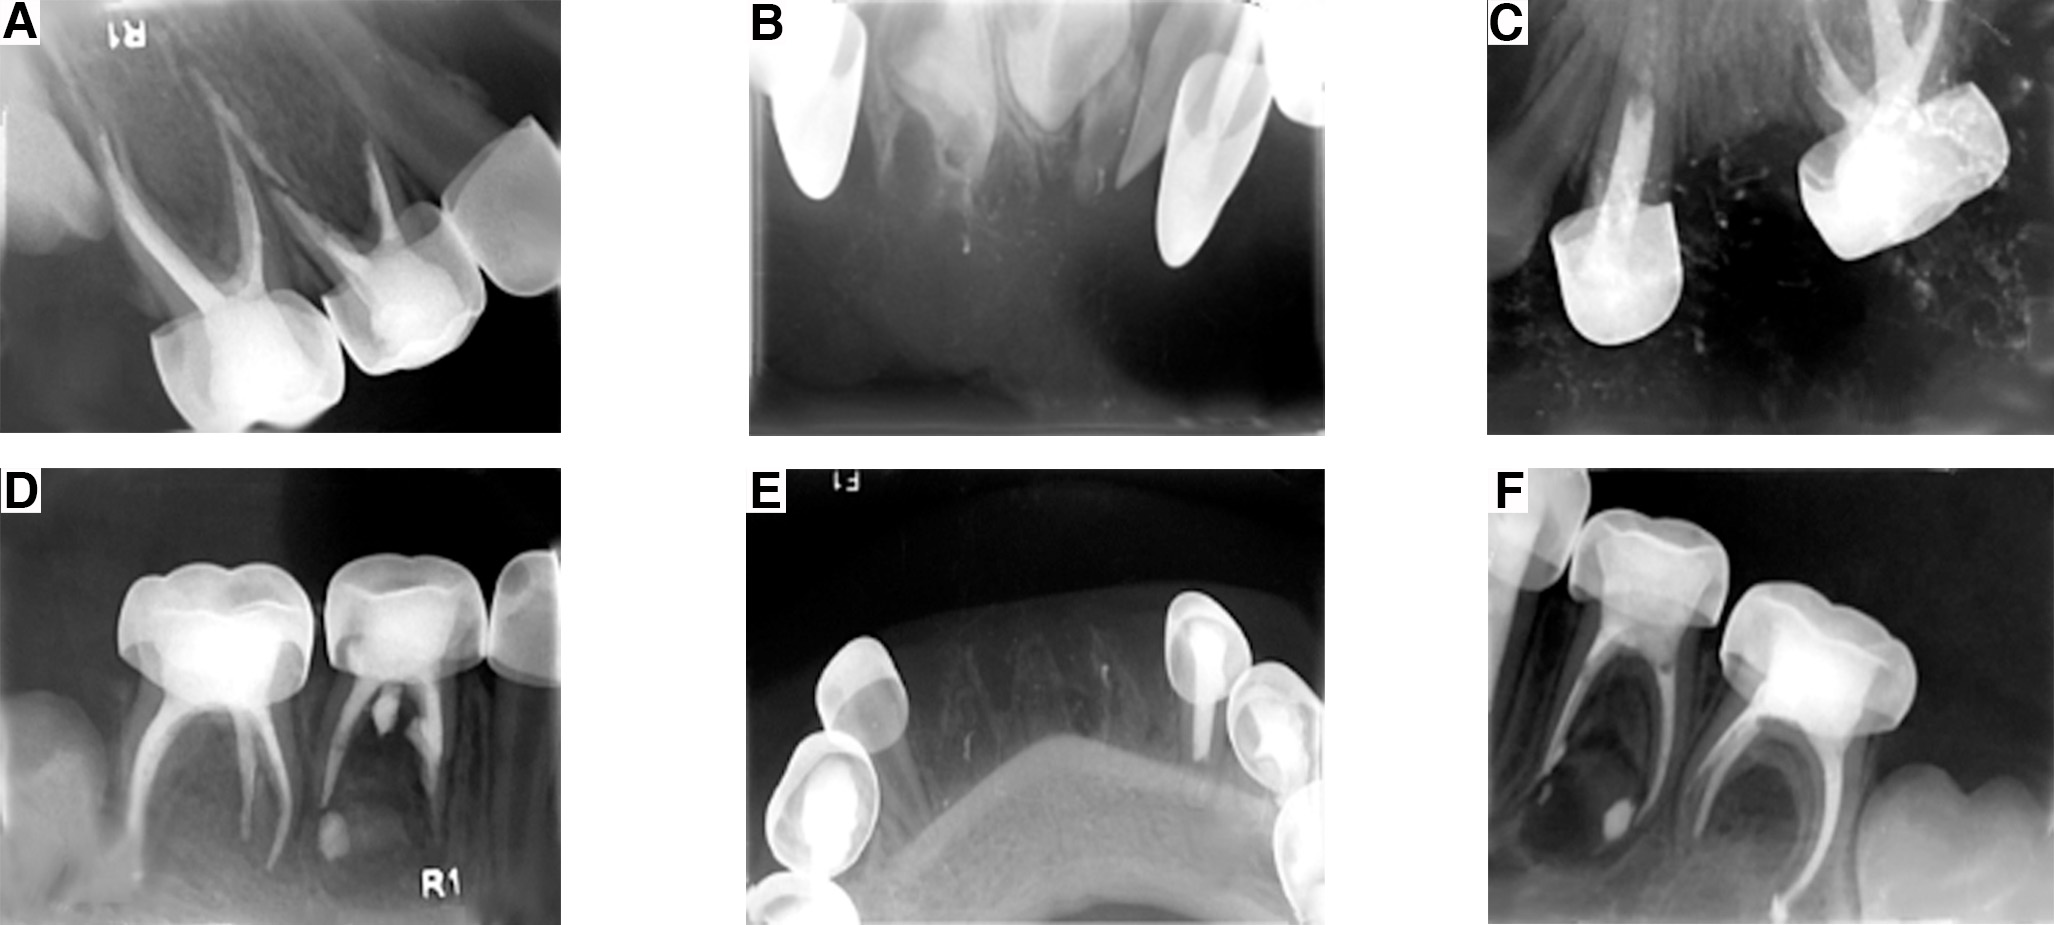

El tratamiento hecho en el quirófano, bajo anestesia general, consistió en pulpectomías llevadas a cabo con un sistema rotatorio, con aislamiento absoluto y coronas de las siguientes piezas infantiles: segundo molar superior derecho, primer molar superior derecho, segundo molar superior izquierdo, canino superior izquierdo, segundo molar inferior izquierdo, primer molar inferior izquierdo, canino inferior izquierdo, segundo molar inferior derecho, primer molar inferior derecho; coronas de las piezas infantiles: canino superior derecho y canino inferior derecho; extracciones de las piezas infantiles: incisivo central superior derecho, incisivo central superior izquierdo, incisivo lateral inferior derecho, incisivo central inferior derecho, incisivo central inferior izquierdo e incisivo lateral inferior izquierdo (figura 5 A, B, C, D, E y F, y figura 6 A, B, C, D y E), todo lo anterior bajo las guías de la Academia Americana de Odontología Pediátrica (AAPD, por sus siglas en inglés). En las citas subsecuentes se colocó un frente estético inferior para mejorar la estética y función de la cavidad oral del paciente.

Figura 5. Serie radiográfica final.